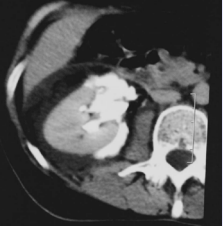

The delayed phase of the contrast enhanced CT scan showed free passage of contrast material from therenal pelvis to around the kidney (Figure 2)

Figure 2 Abdominal CT with contrast enhanced. Free passage of contrast material from the left renal pelvis to around the kidney and spontaneous rupture of the renal pelvis.